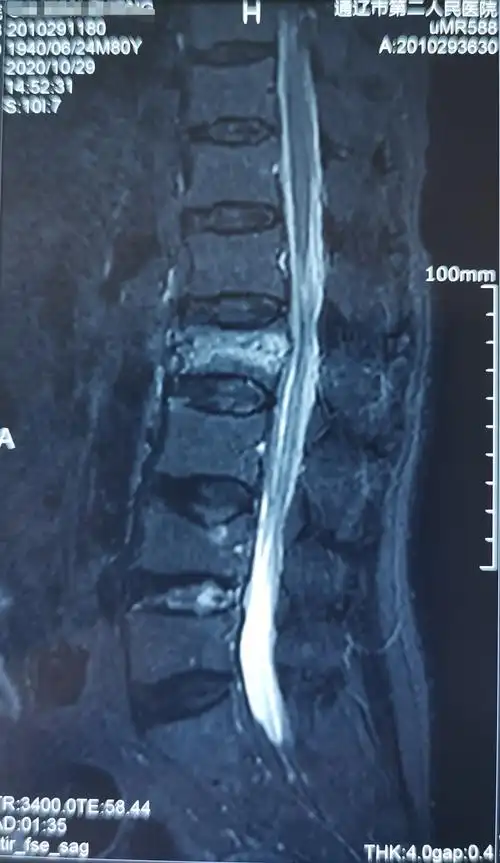

腰2椎体压缩性骨折,闭合复位微创经皮钉棒系统内固定手术治疗.